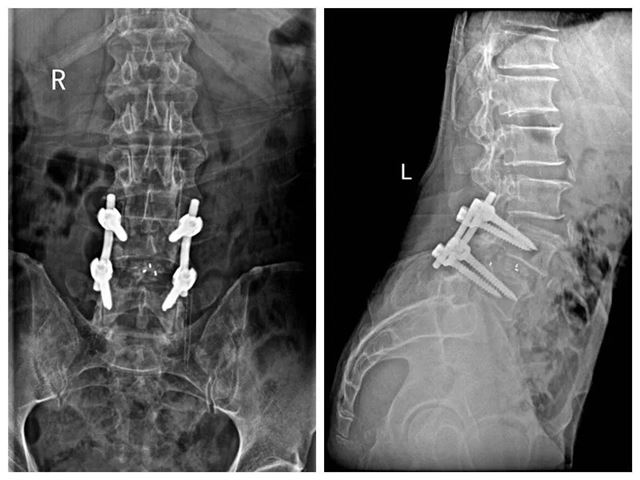

术后摄片

为保证手术安全,医院特邀湖南省骨科专家雷青教授亲临指导手术,经过几个小时努力,曾爷爷成功完成了腰4/5节段切开椎板切除椎管及神经根管减压+椎间盘摘除+椎间融合+后路钉棒系统内固定术。手术顺利,术中出血少,术后无并发症发生。